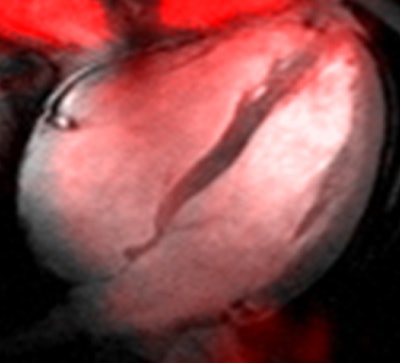

Sodium image of the human heart (in red) acquired at 7 tesla superimposed to an anatomic hydrogen MR image of a four chamber view of the heart. Image courtesy of Thoralf Niendorf, Ph.D.Niendorf is a professor for experimental ultrahigh-field MR at Charité University Medicine, and heads the BUFF Max Delbrück Center for Molecular Medicine.